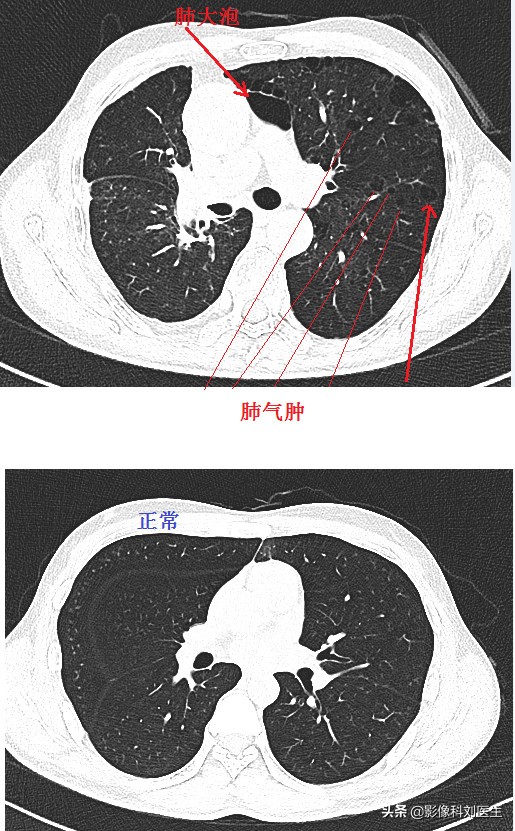

首先给大家看几张CT图像:

通过上面的图像,相信大家有了一个大概的印象。肺气肿主要征象即为正常肺组织内出现无囊壁的低密度区。

第三,间隔旁型肺气肿。它通常与其他类型的肺气肿合并存在。它的危险因素也是吸烟;主要位于胸膜下,容易造成气胸。在CT上表现为多发、单层胸膜下局限性透亮区,通常在1.0cm以下,常常伴有小叶中央型肺气肿或肺大泡。